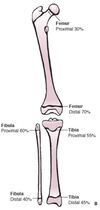

Percentual de crescimento dos MMII?

26